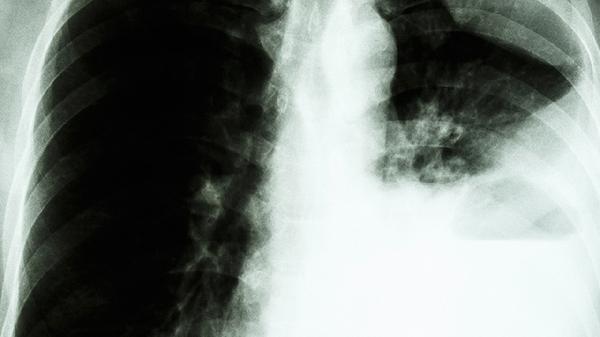

清肺散结丸可用于肺结节患者。肺结节是指肺部出现的小于30毫米的圆形或类圆形病灶,可能与长期吸烟、空气污染、肺部感染等因素有关,患者可能出现咳嗽、胸痛等症状。药物中的三七能帮助活血化瘀,浙贝母可清热化痰,但需配合胸部CT定期复查。常用剂量为医生根据结节大小及症状调整,避免与辛辣刺激性食物同服。

职业性尘肺患者适合使用清肺散结丸缓解症状。尘肺是由于长期吸入矿物性粉尘导致的肺部纤维化,表现为进行性呼吸困难、咳嗽伴黑色痰液。该药能减轻肺部炎症反应,但需联合氧疗或肺泡灌洗等治疗。合并肺心病者慎用,服药期间应脱离粉尘环境并定期进行肺功能检查。